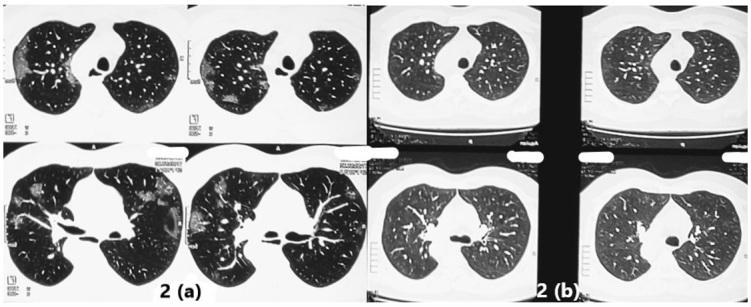

酷似间质性肺疾病的新冠后综合征:病例系列

Long COVID Mimicking Interstitial Lung Disease: A Case Series.

Interstitial lung diseases (ILD) can occur due to various known or unknown causes. They usually present with dry cough and exertional dyspnea. On radiology usual findings are ground glass opacities (GGO's), reticular shadows, nodules etc. Some patients after acute COVID-19 (coronavirus disease 2019) suffer from persistent symptoms/manifestations. These have been called 'Long COVID'. Long COVID also has radiological features like GGO's, nodules and reticulations. Further, patients even without history of acute COVID-19, can also present with 'Long COVID'. In the present case series, we describe three such cases with no history of having suffered from COVID-19, presenting with ILD like features and diagnosed as Long COVID. We infer from these cases that 'Long COVID' can both clinically and radiologically mimic ILD's. Hence, emphasizing the fact that in the present COVID-19 pandemic situation, 'Long COVID should be a differential diagnosis to be considered while making a new diagnosis of ILD.

摘要

间质性肺疾病(ILD)可由各种已知或未知原因引起。它们通常表现为干咳和劳力性呼吸困难。在放射学上,常见表现为磨玻璃影(GGO)、网状阴影、结节等。一些急性新型冠状病毒肺炎(COVID-19,冠状病毒病2019)患者会出现持续症状/表现。这些被称为“长新冠”。“长新冠”也有放射学特征,如磨玻璃影、结节和网状影。此外,即使没有急性COVID-19病史的患者也可能出现“长新冠”。在本病例系列中,我们描述了3例无COVID-19病史、表现出ILD样特征并被诊断为“长新冠”的病例。我们从这些病例中推断,“长新冠”在临床和放射学上都可能酷似ILD。因此,强调在当前COVID-19大流行情况下,“长新冠 ”应作为新诊断ILD时需考虑的鉴别诊断。